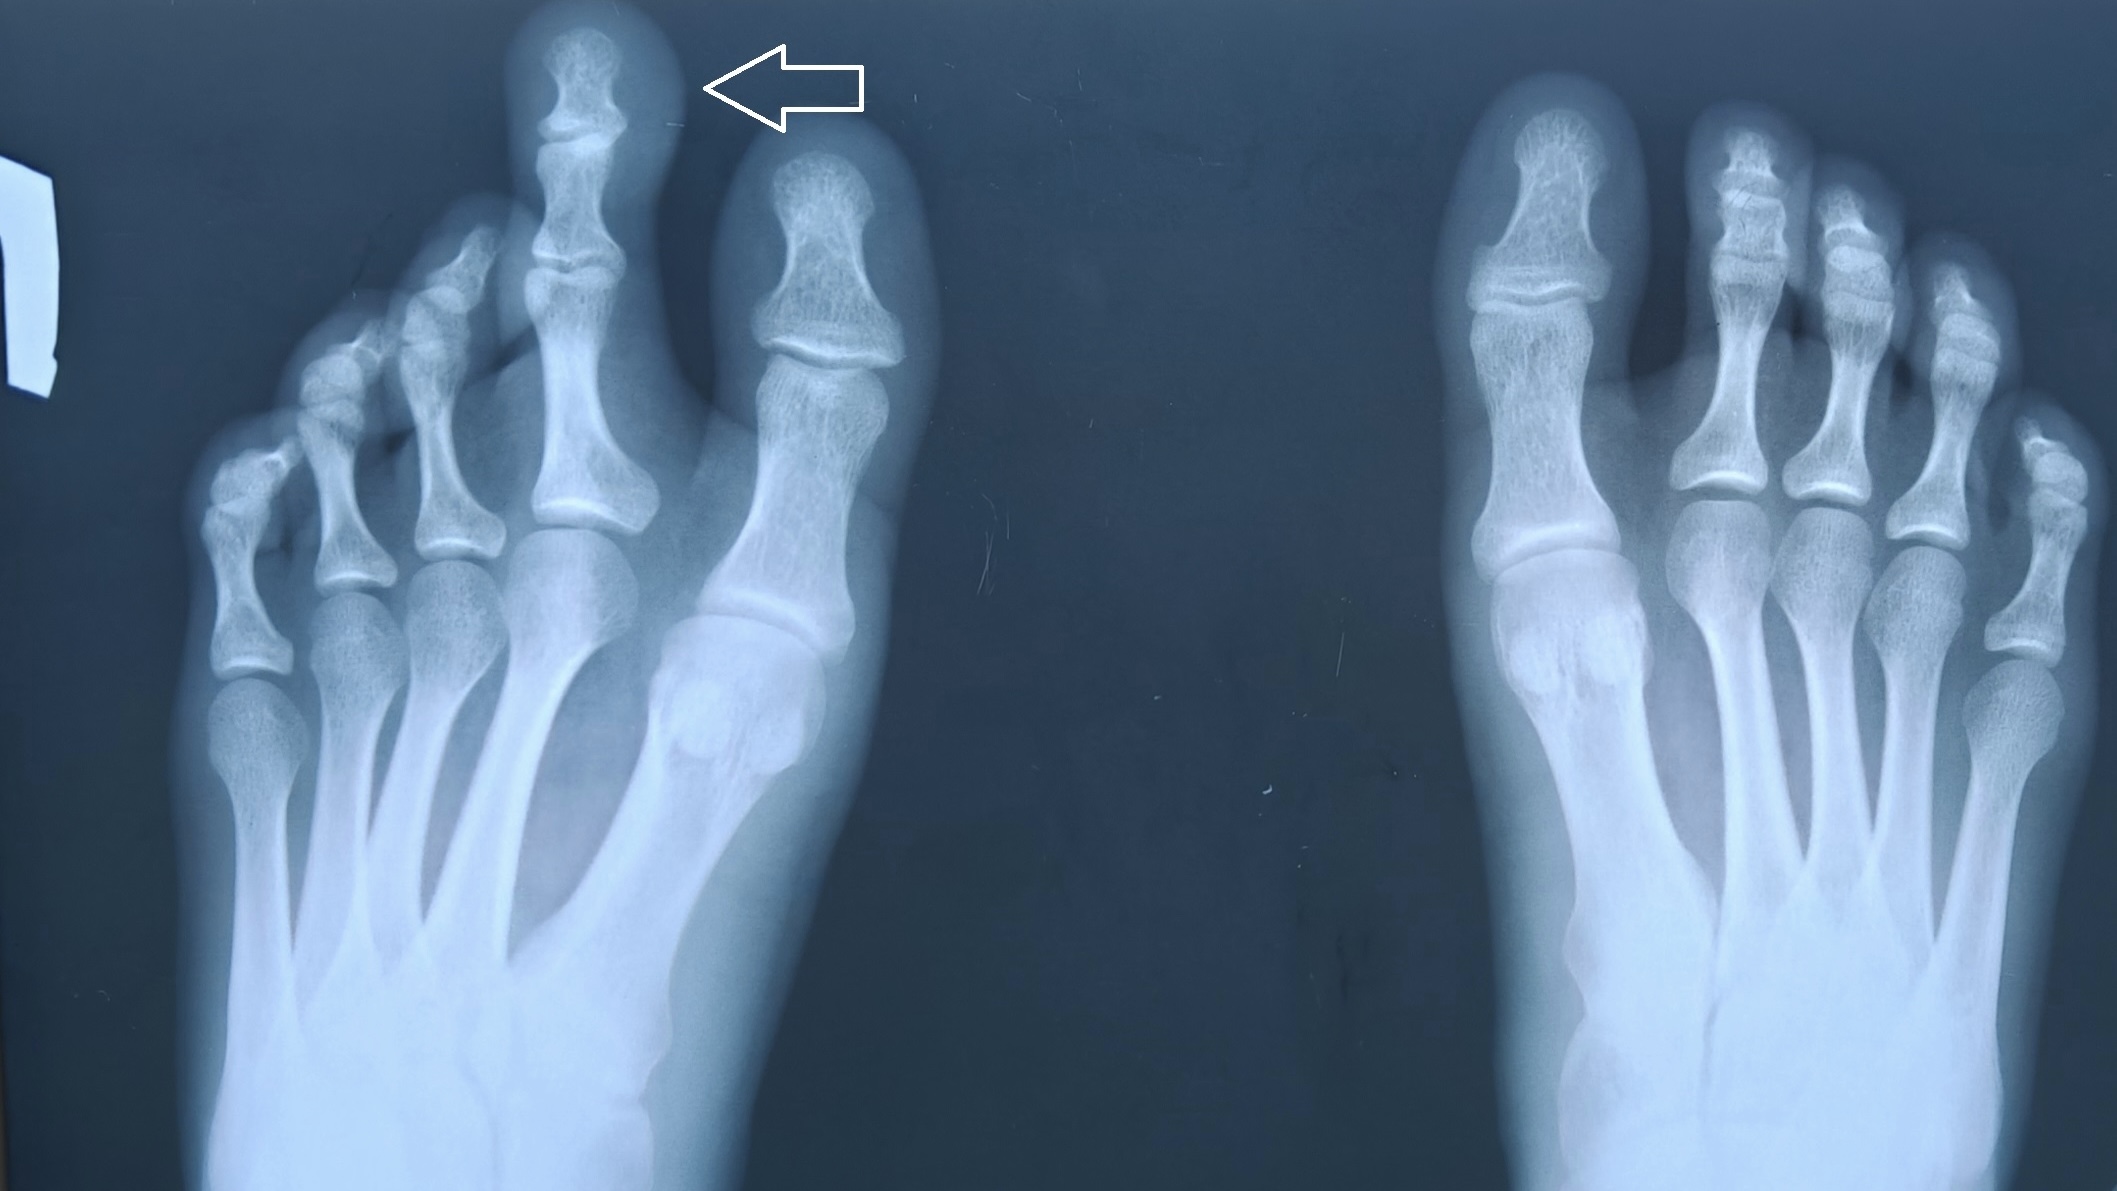

Пациентка обратились со значительным увеличением второго пальца левой стопы. Основной жалобой был косметический дефект, а также трудности с подбором обуви.

Медики выполнили операцию – укорачивающую остеотомию с фиксаций костных фрагментов спицей и удаление избыточных мягких тканей. В итоге был сформирован косметически и функционально полноценный палец.